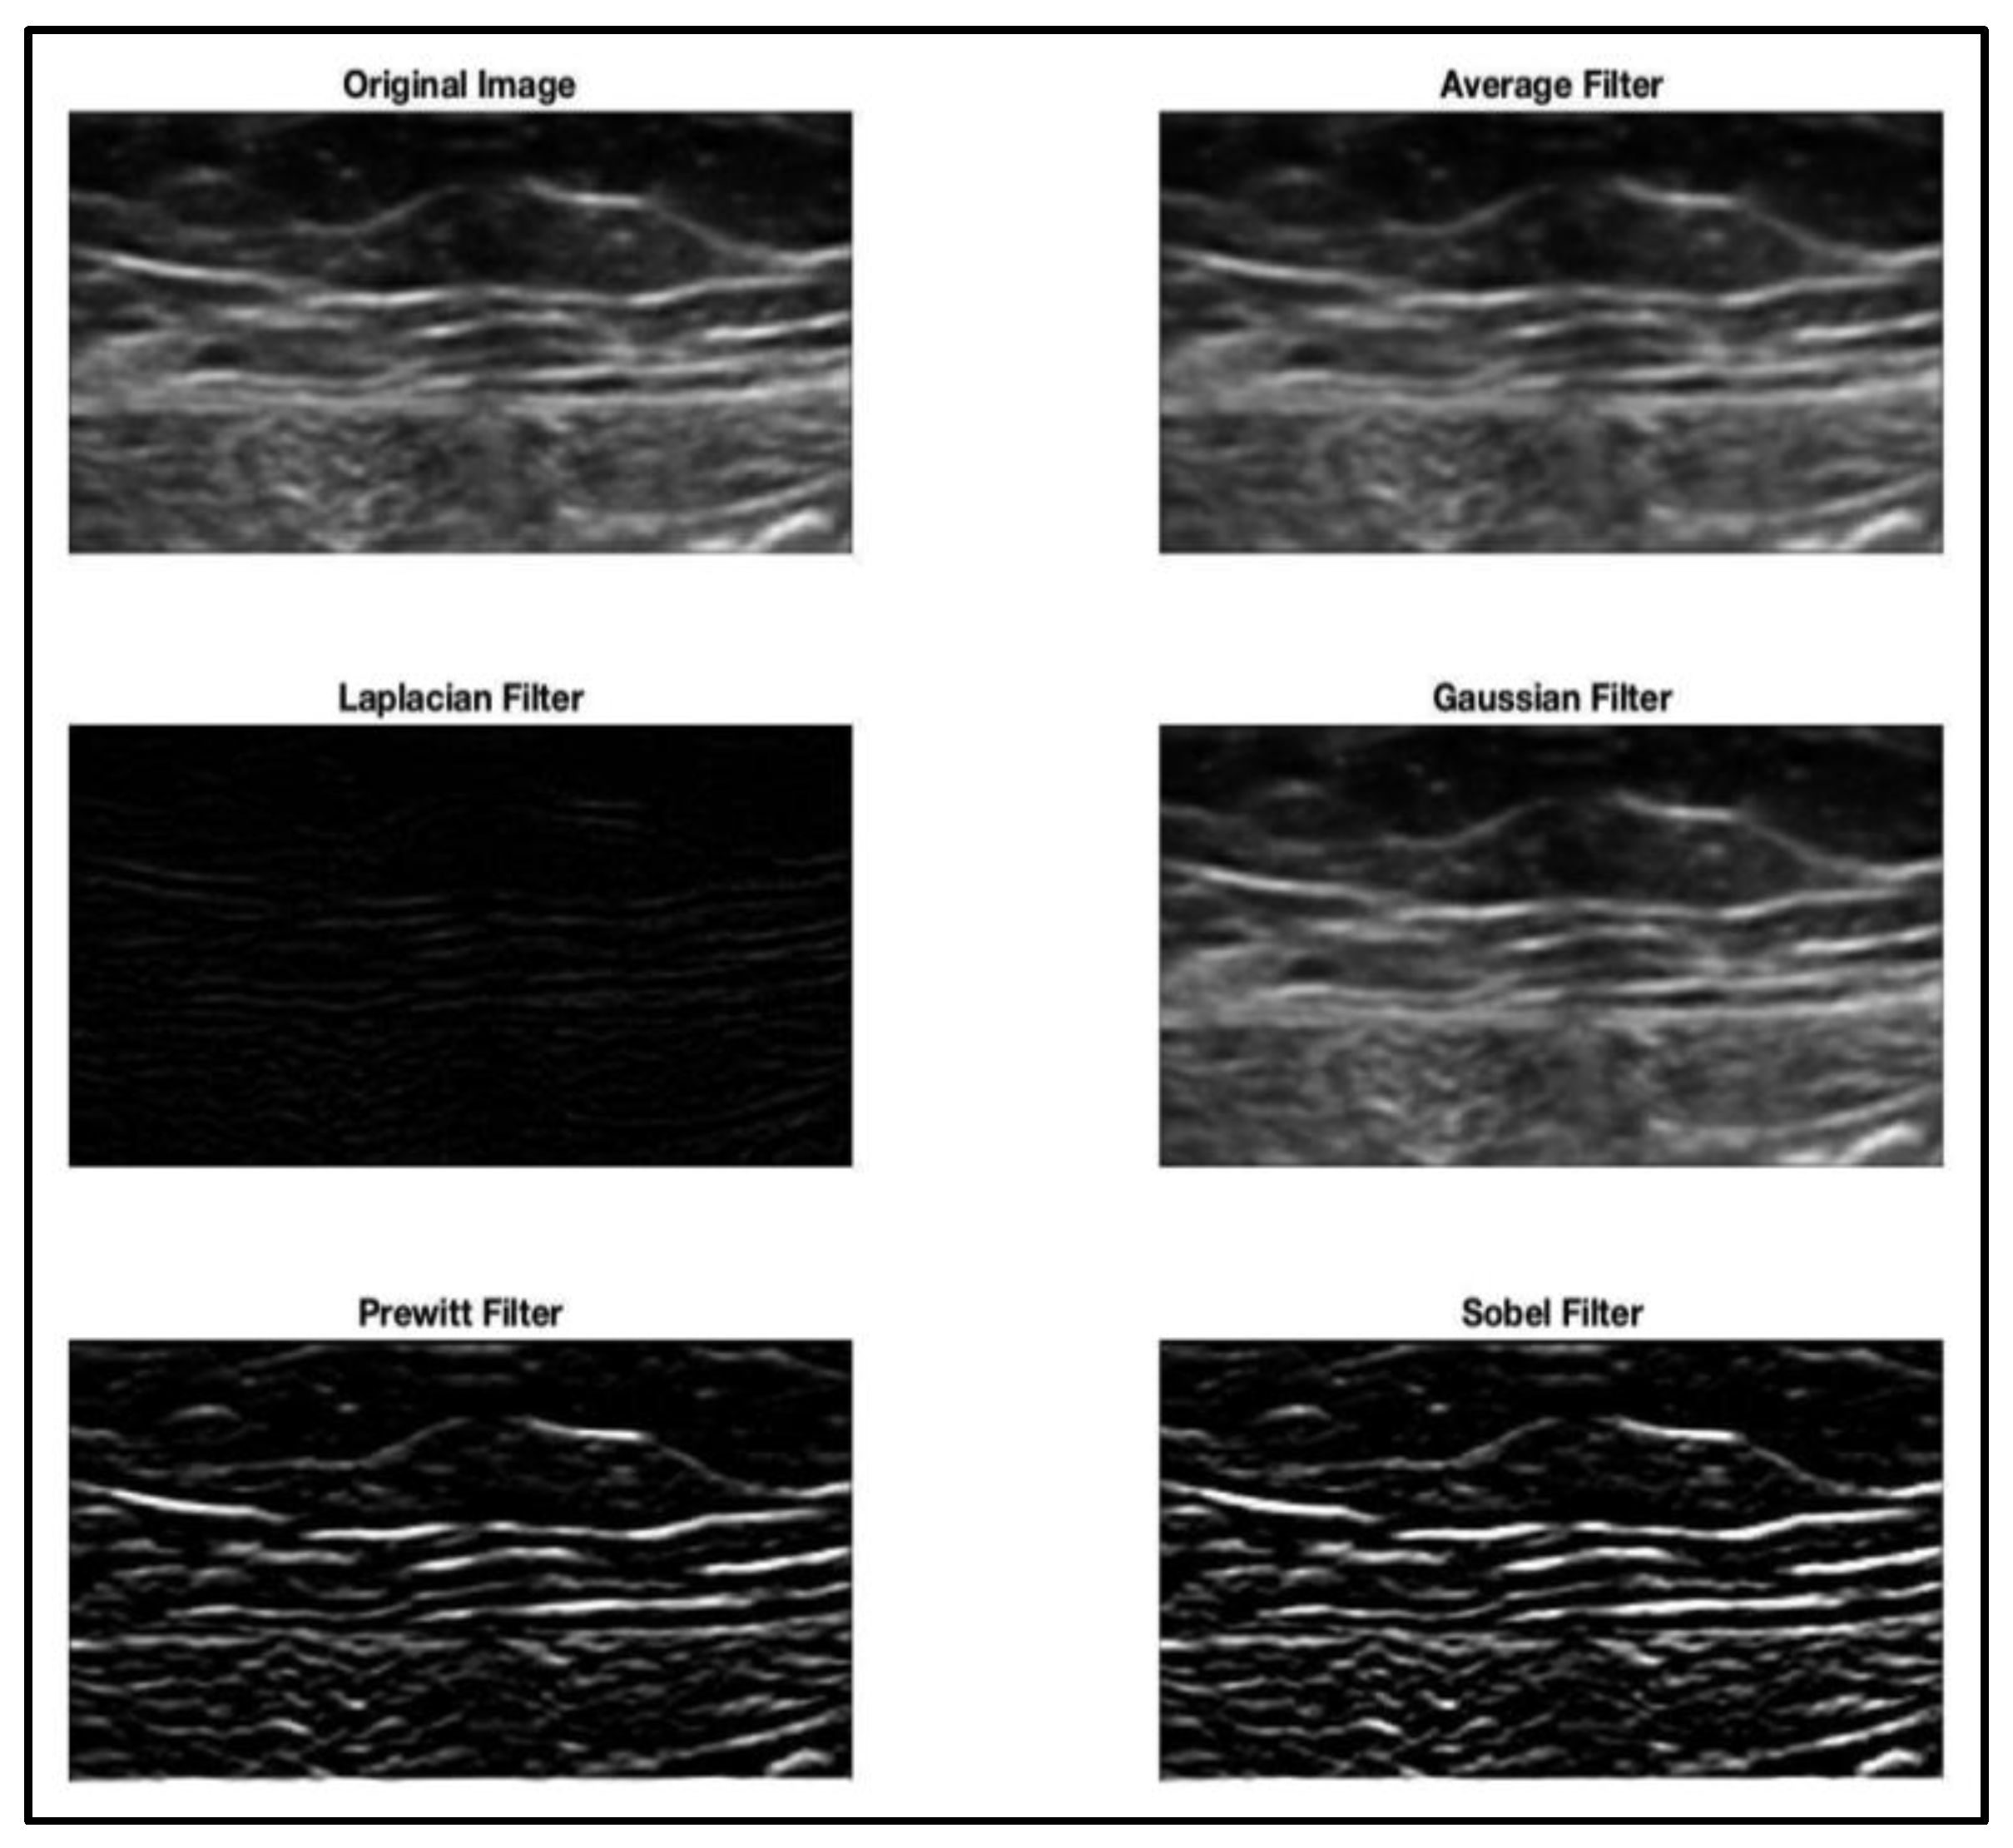

| Normalization/histogram equalization | [1,12,13,15,17,18,19,25,26,28,31,32,33,39,40,55,59,60,61,63,70,73,80,85,86,90,91,104] |

| Intensity-based/dimensional-based filtering | [3,6,12,17,28,54,70,86] |